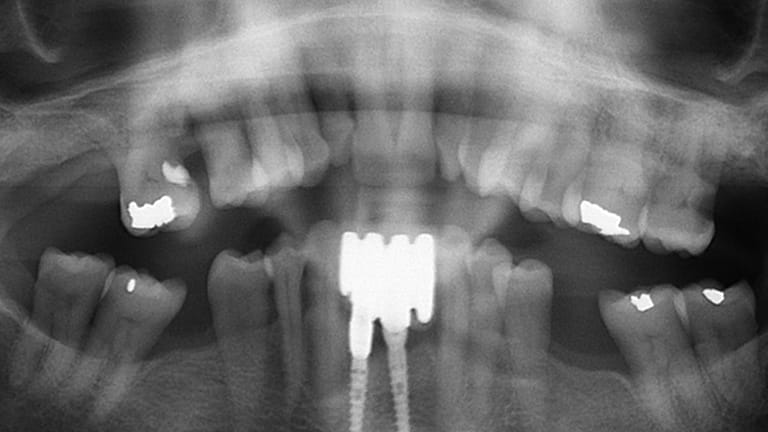

Bad Tooth

Implant (With no crown)

Implant with crown